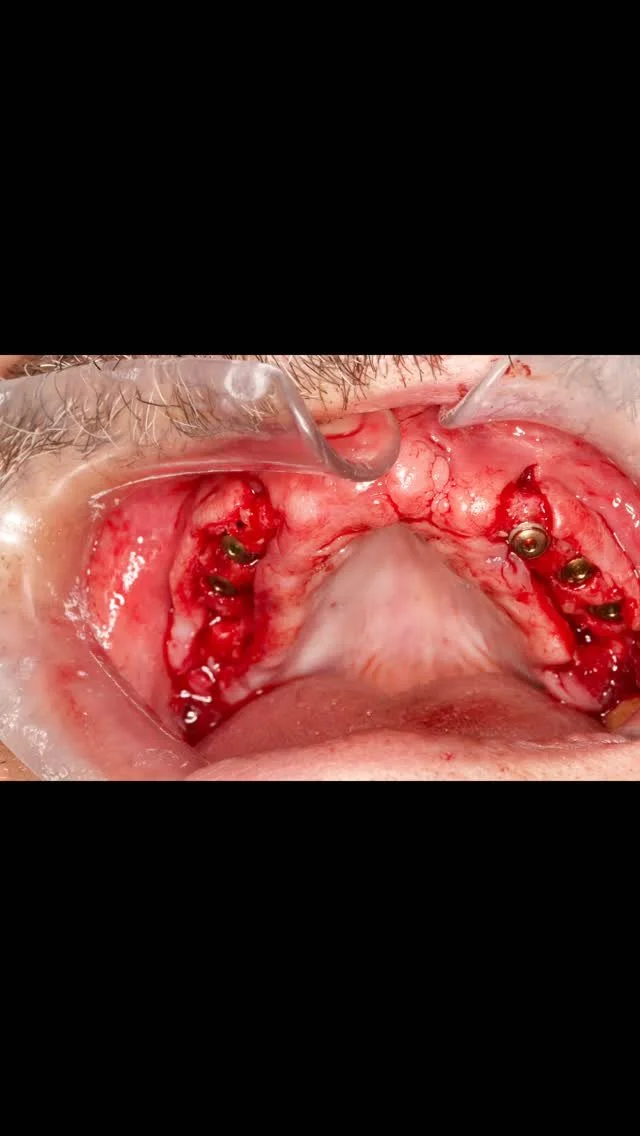

At Sky Dental Clinic, we are committed to providing personalized, state-of-the-art dental care. Led by Dr. Faisal Mohammad Ali Qaoud, a specialist in dentistry and facial aesthetics, our clinic offers a wide range of services including cosmetic dentistry, periodontal surgery, teeth whitening, and Hollywood smile treatments. With a focus on the latest advancements in dental technology, we strive to deliver tailored solutions that meet the unique needs of each patient.

At our dental practice, we are committed to delivering exceptional care with a focus on precision, technology, and patient comfort. Our team of experts strives to exceed your expectations by providing personalized treatments tailored to your oral health needs.